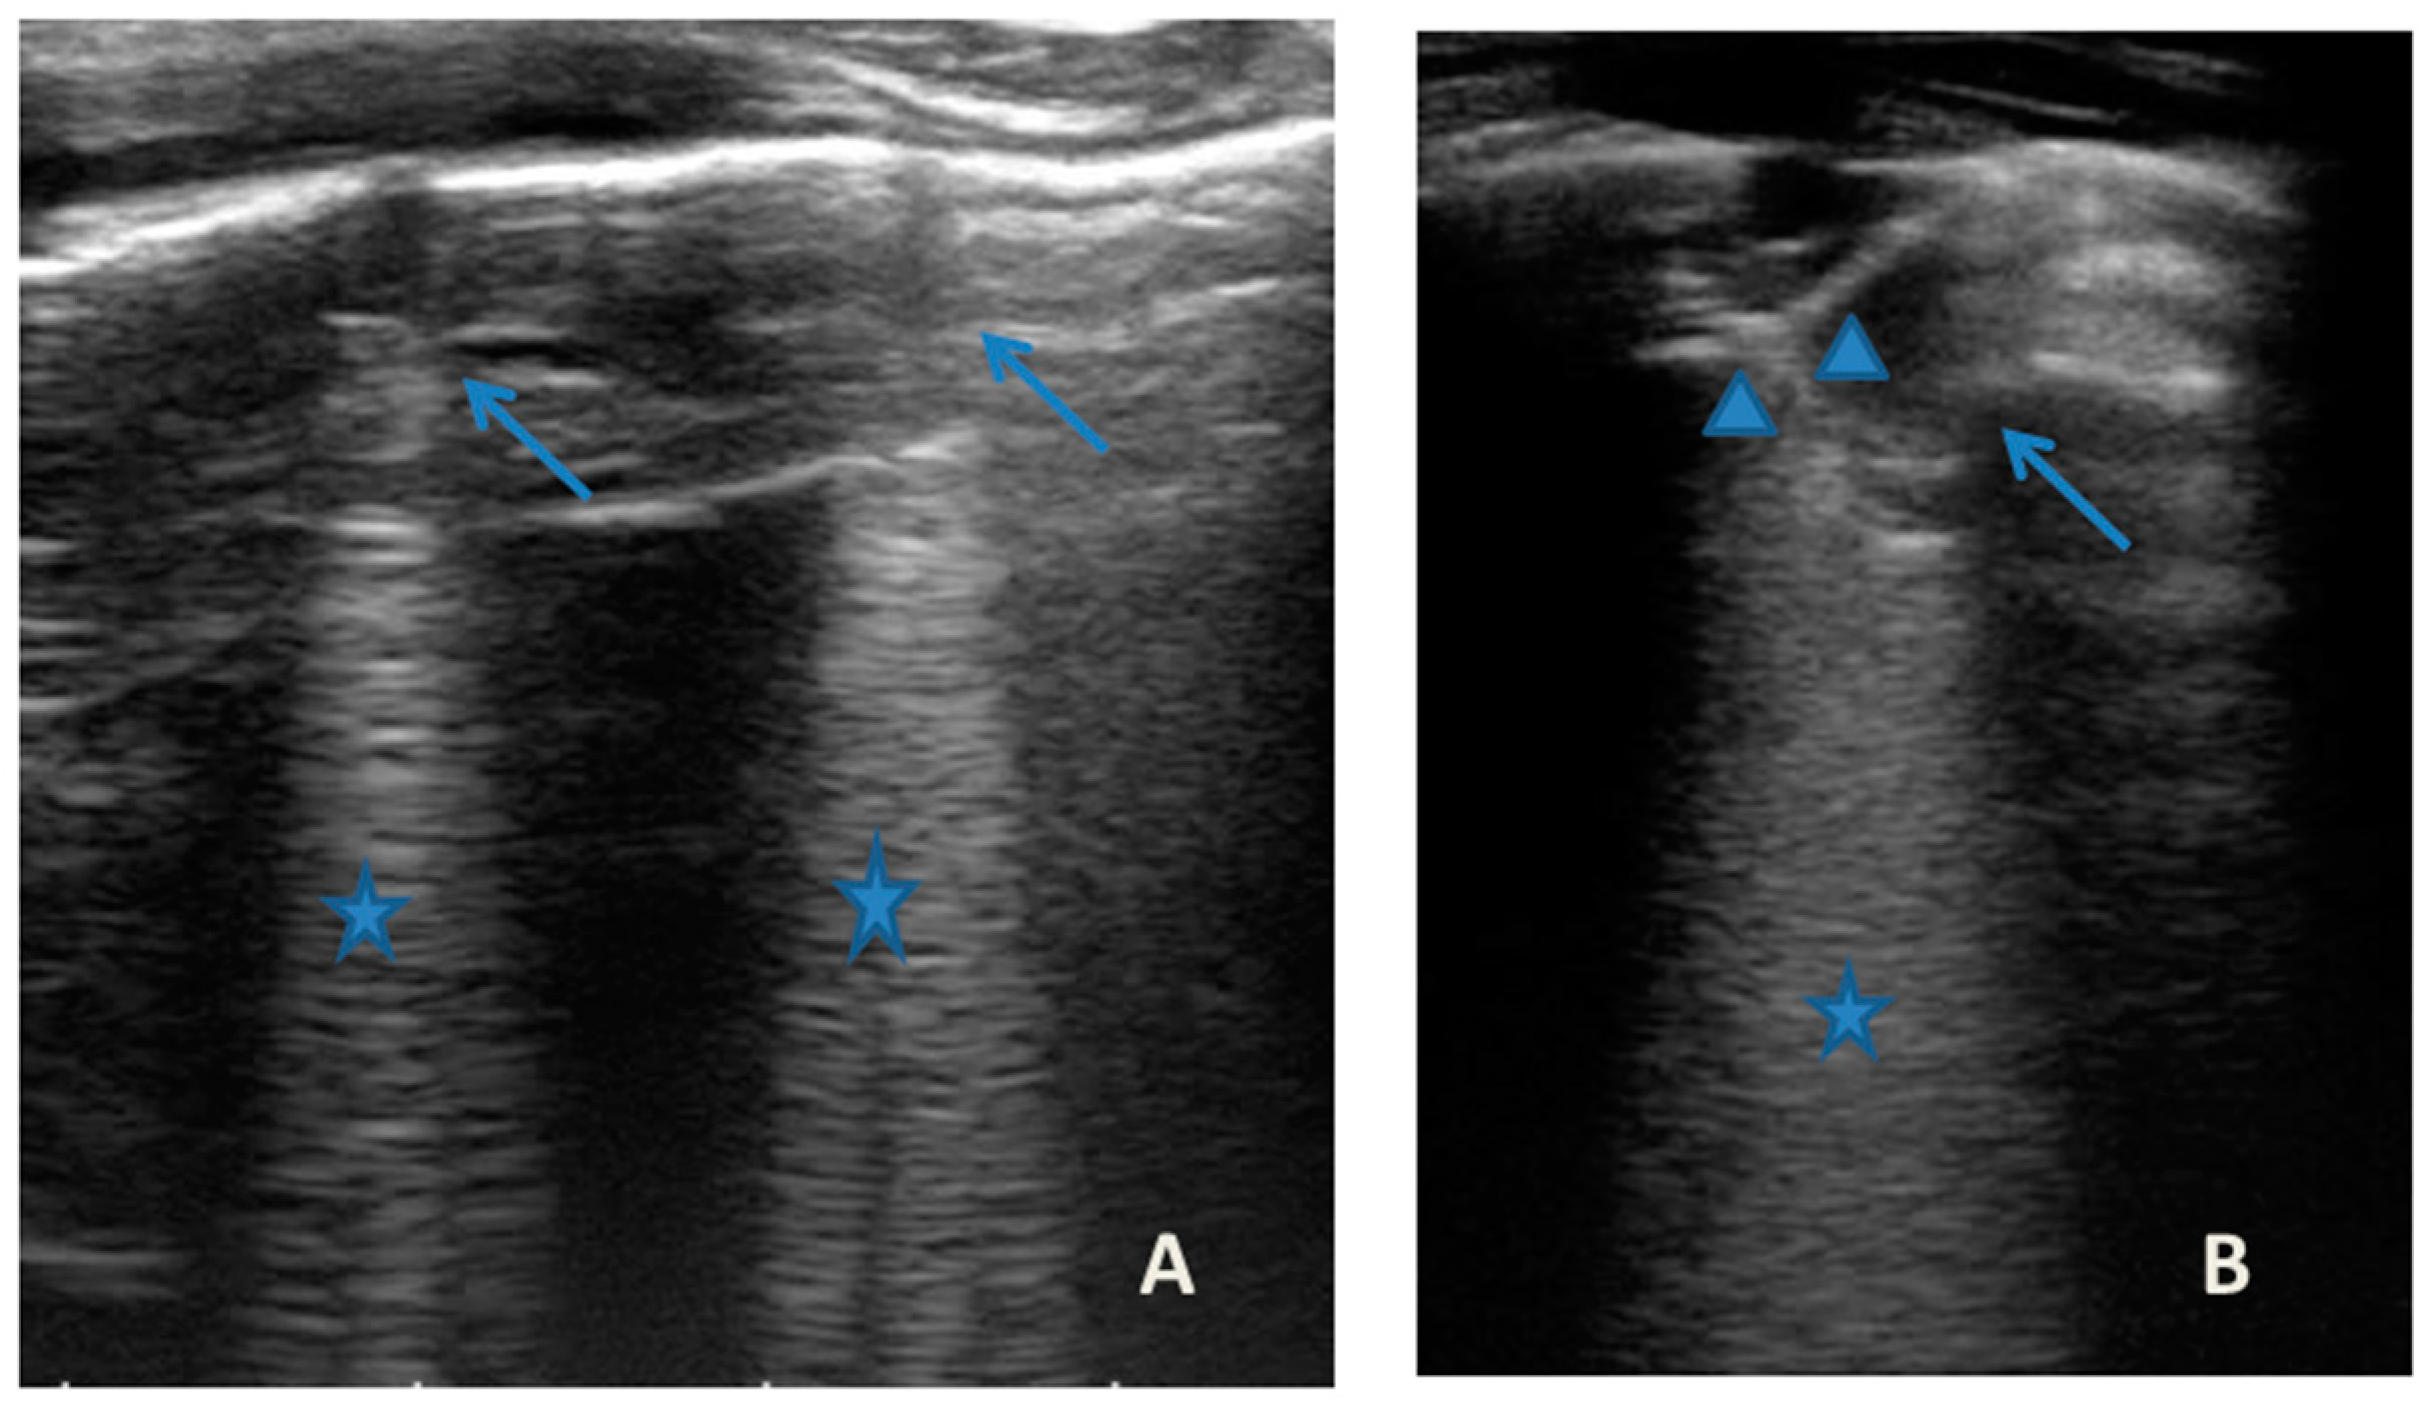

Case 6 was a 10-year-old girl with a medical history of allergic rhinoconjunctivitis recurring since childhood; her diagnosis of allergic asthma (T2-eosinophilic phenotype— “T2-high” [11,12]) was from 6 years of age. It has always been a severe phenotype despite adequate preventive therapy, so much as to require a progressive step-up of the therapy itself up to the maximum step [1,2,3]. Despite this, and the good adherence to therapy, she came to our attention at the pediatric allergy clinic of our hospital, reporting that she was still having recurrent symptoms, resorting daily to short-acting bronchodilators, and was also having nocturnal symptoms. She had an ACT of 20 points [13], and pathological control spirometry. Therefore, in consideration of the presence of severe eosinophilic T2 allergic asthma (T2-high), the patient was a candidate for the administration of a biological drug. However, before classifying the patient as such, a chest CT was performed to exclude the presence of other pathological respiratory conditions that could dissemble asthma (Figure 8).

Figure 8.

A representative coronal section from thoracic computed tomography (CT) scan reveals: thickening of the bronchial walls bilaterally, with filling of the bronchial lumen predominantly in the apical segment of the right upper lobe; picture of diffuse inhomogeneity of parenchymal density with diffuse and bilateral hypodense areas in relation to air trapping correlated to a picture of recurrent airway inflammation.

LUS was also performed, which showed a picture compatible with the features detected on CT (Figure 9).

Furthermore, evaluating some patients who had important ultrasound lesions (such as atelectasis of a certain entity, or diffuse sonographic interstitial syndrome), as in the first three cases, we wondered if some of these lesions may have already been present before the acute attack, and also in consideration of the finding of a positive ultrasound picture even in the stability phase, and after starting an adequate preventive therapy. Hence, there is a need to take into account the asthmatic phenotype and its severity for all patients, and also to evaluate the ultrasound patterns of patients in the stability phase in an outpatient setting, as in case 6. In the latter case—a patient with allergic asthma severe eosinophilic atopic type 2, but in a stability phase—the chest CT (Figure 8) showed signs of airway and lung parenchyma remodeling compatible with the patient’s severe clinical picture. LUS (Figure 9) showed a picture of diffuse short vertical artifacts, long confluent and non-confluent artifacts, and irregularities of the pleural line and sub-centimeter consolidations: lesions that, in the absence of acute respiratory pathology (as in our case), could be compatible with the remodeling pattern found on the chest CT.